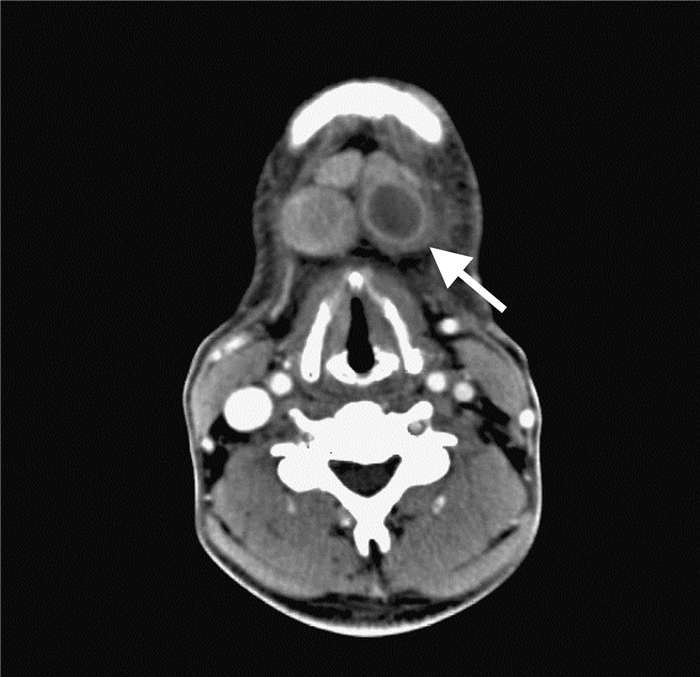

(Слева) КТ с КУ, аксиальная проекция. Патологическое образование поднижнечелюстного пространства, расположенное кпереди от лицевой вены. Такая локализация характерна для лимфоузлов уровня lb. Поднижнечелюстная слюнная железа лежит кзади от лицевой вены. Узлы, расположенные кзади от железы, относятся к уровню II.

(Справа) КТ с КУ, аксиальная проекция. Новообразование латеральной поверхности шеи слева, расположенное глубже от грудино-ключично-сосцевидной мышцы. Нечеткие контуры и разрушение границ между жировой клетчаткой и мышцей говорят о наличии экстракапсулярного распространения, четкого признака злокачественного процесса. (Слева) КТ с КУ, аксиальная проекция. Выраженное увеличение лимфоузла II уровня. Если судить только по размеру, лимфоузел является злокачественным; но его почкообразная форма говорит в пользу доброкачественности процесса (реактивный узел).

На ниже представленном КТ снимке визуализируется некроз лимфатических узлов группы IA.

На ниже представленном КТ снимке визуализируется лимфаденопатия группы IB справа.